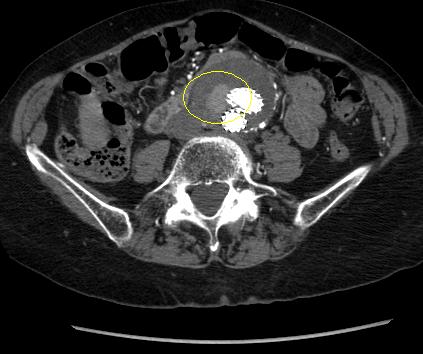

Tipo I:

Vazamento no local de afixação (tipo IA na extremidade proximal da endoprótese ou oclusor da ilíaca; tipo IB na extremidade distal); geralmente imediatos, mas podem ocorrer vazamentos tardios.[Figure caption and citation for the preceding image starts]: Vazamento (endoleak) do tipo I na anastomose ilíaca esquerda distal (vazamento circulado)University of Michigan, mais especificamente os casos do Dr. Upchurch, representando os Departamentos de Cirurgia vascular e Radiologia [Citation ends].

Deve-se fazer todo o esforço possível para reparar vazamentos (endoleaks) do tipo I antes de finalizar o procedimento (por exemplo, moldagem por balão da zona de vedação proximal, colocação de um manguito proximal, grampeamento interno, embolização líquida).[248] Para os pacientes com comprometimento da selagem proximal após um reparo endovascular do aneurisma da aorta abdominal, deve-se considerar uma extensão proximal com dispositivos fenestrados e ramificados.[2] Um endoleak do tipo IA persistente pode necessitar de conversão para reparo aberto, desde que o risco cirúrgico seja aceitável.[2][77][249][Figure caption and citation for the preceding image starts]: Enxerto de endoprótese de extensão implantado para o mesmo vazamento (endoleak) do tipo I (circulado)University of Michigan, mais especificamente os casos do Dr. Upchurch, representando os Departamentos de Cirurgia vascular e Radiologia [Citation ends].